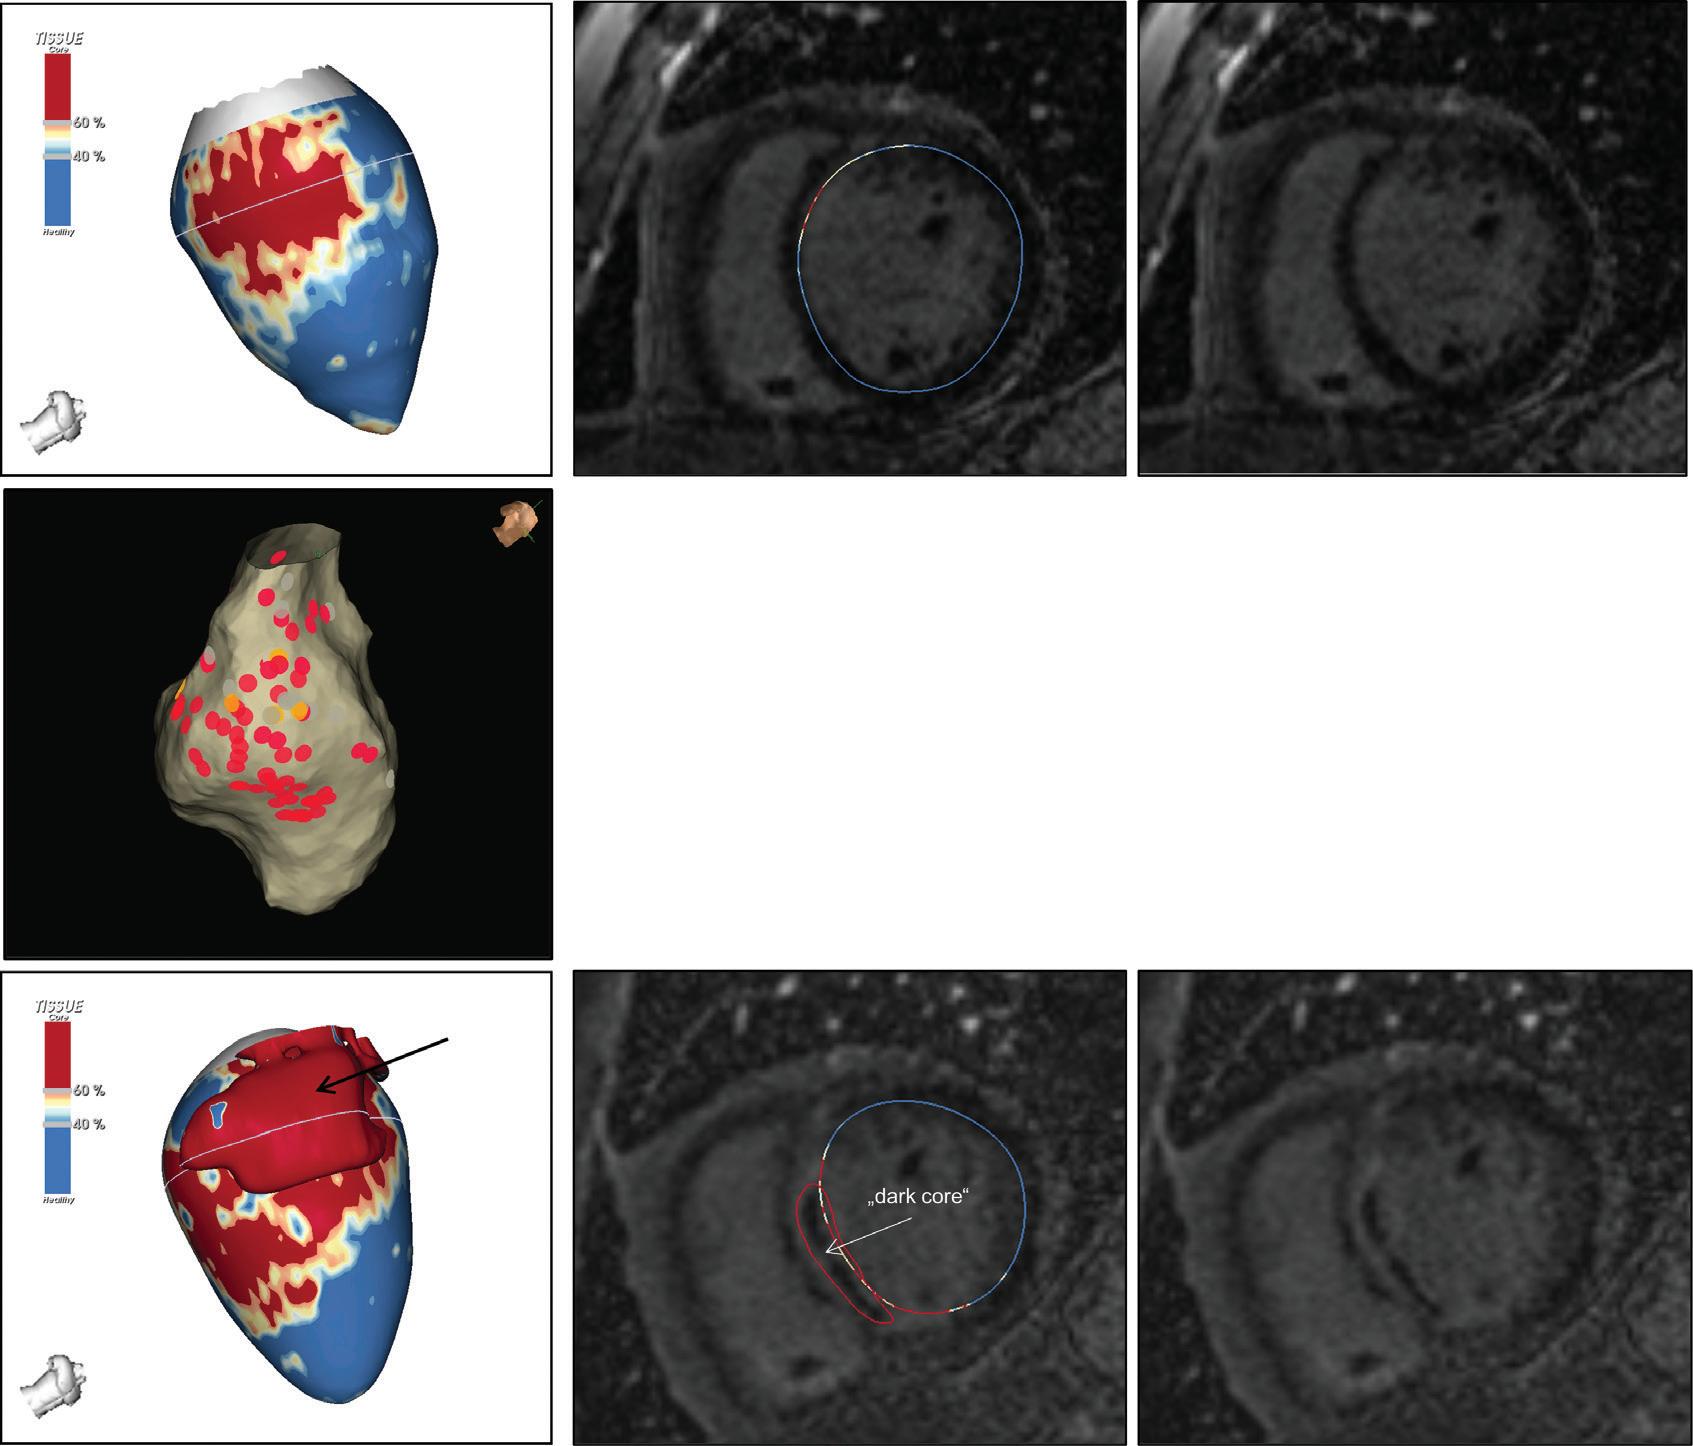

Figure 7: Assessing Elimination of Arrhythmogenic Fibrotic Substrate by Late Gadolinium Enhancement-MRI

Against this background, we have recently analysed the potential role of LGE-MRI to assess the long-term effect of VT ablation in terms of arrhythmogenic substrate elimination (unpublished data). Three to 6 months following the procedure, effective ablation was reflected by pronounced reduction of LGE-MRI-detected border zone scar volume and extent of slow conduction channels compared to the preprocedural LGEMRI (Figure 7). In patients undergoing repeat ablation procedures, this arrhythmogenic substrate elimination as determined by LGE-MRI correlated well with EAM. Thus, LGE-MRI-based lesion assessment may be of potential value to evaluate the efficacy of ventricular substrate ablation and to predict VT recurrences and clinical outcome. However, as mentioned above, clinical validation is warranted.

Left panel: LGE map of the left ventricle prior to substrate-based ventricular tachycardia ablation. LGE depicts an antero-apical scar. A 3D-analysis using the ADAS 3D software predicts a slow-conduction channel (black line) extending over 30 % of the transmurality that was confirmed by invasive electroanatomical mapping. Right panel: LGE map of the left ventricle 3 months post-ventricular tachycardia ablation. LGE indicates complete scar homogenisation and ‘dechannelling’ with ablation lesions covering the full substrate. Percentages indicate distinct layers of the transmurality from endocardial (0%) to epicardial (100%). LGE = late gadolinium enhancement.